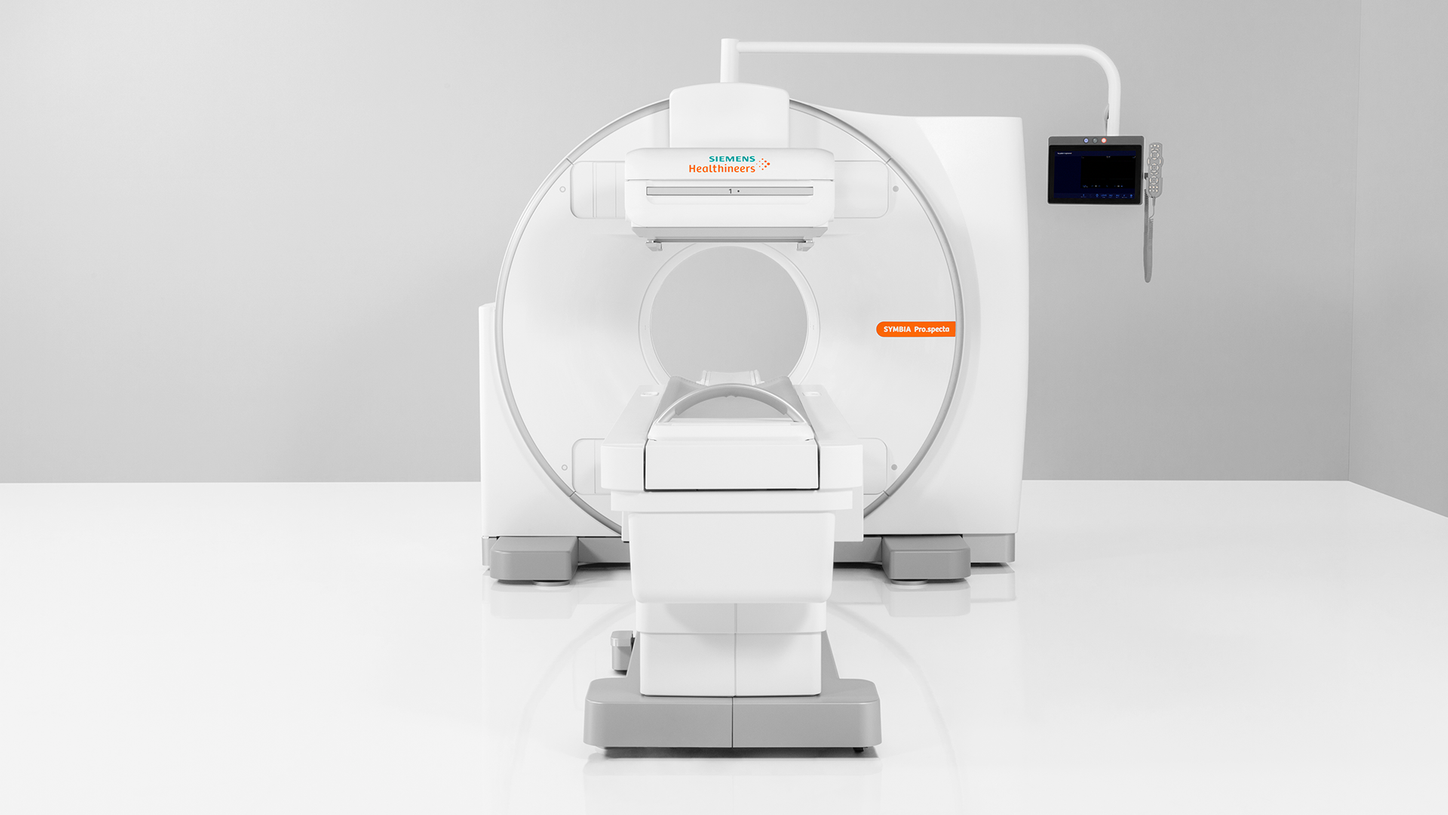

Answering to clinical needs in oncology, neurology, cardiology, and radiology, Siemens Healthineers Molecular Imaging systems provide PET/CT, SPECT, and hybrid SPECT scanner (SPECT/CT) solutions to help clinicians diagnose, treat, and monitor diseases more confidently.